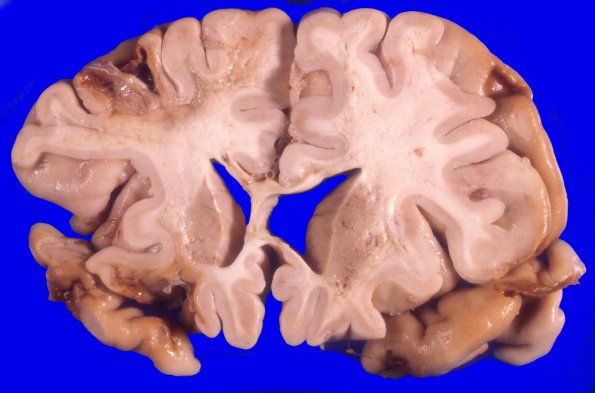

17A5 Trauma, Baseball bat (Case 17) 7

Multiple coronal sections demonstrating many severe contusive injuries with underlying loss of white matter.